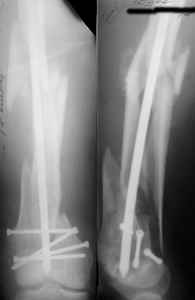

At that moment we had in stock only the 10 mm solid nails so of course there was no idea about early weight bearing. But it was quite enough for early knee ROM excersises (see attached). Two locking screws through the distal block provided that.

A new toy is more interesting and fashionable. And anyway it is not panacea, i have already seen presentations with LISS failures like the attached one presented by D.Seligson. And people also demonstrated incisions say that the method is not so LESS invasive as it supposed to be.